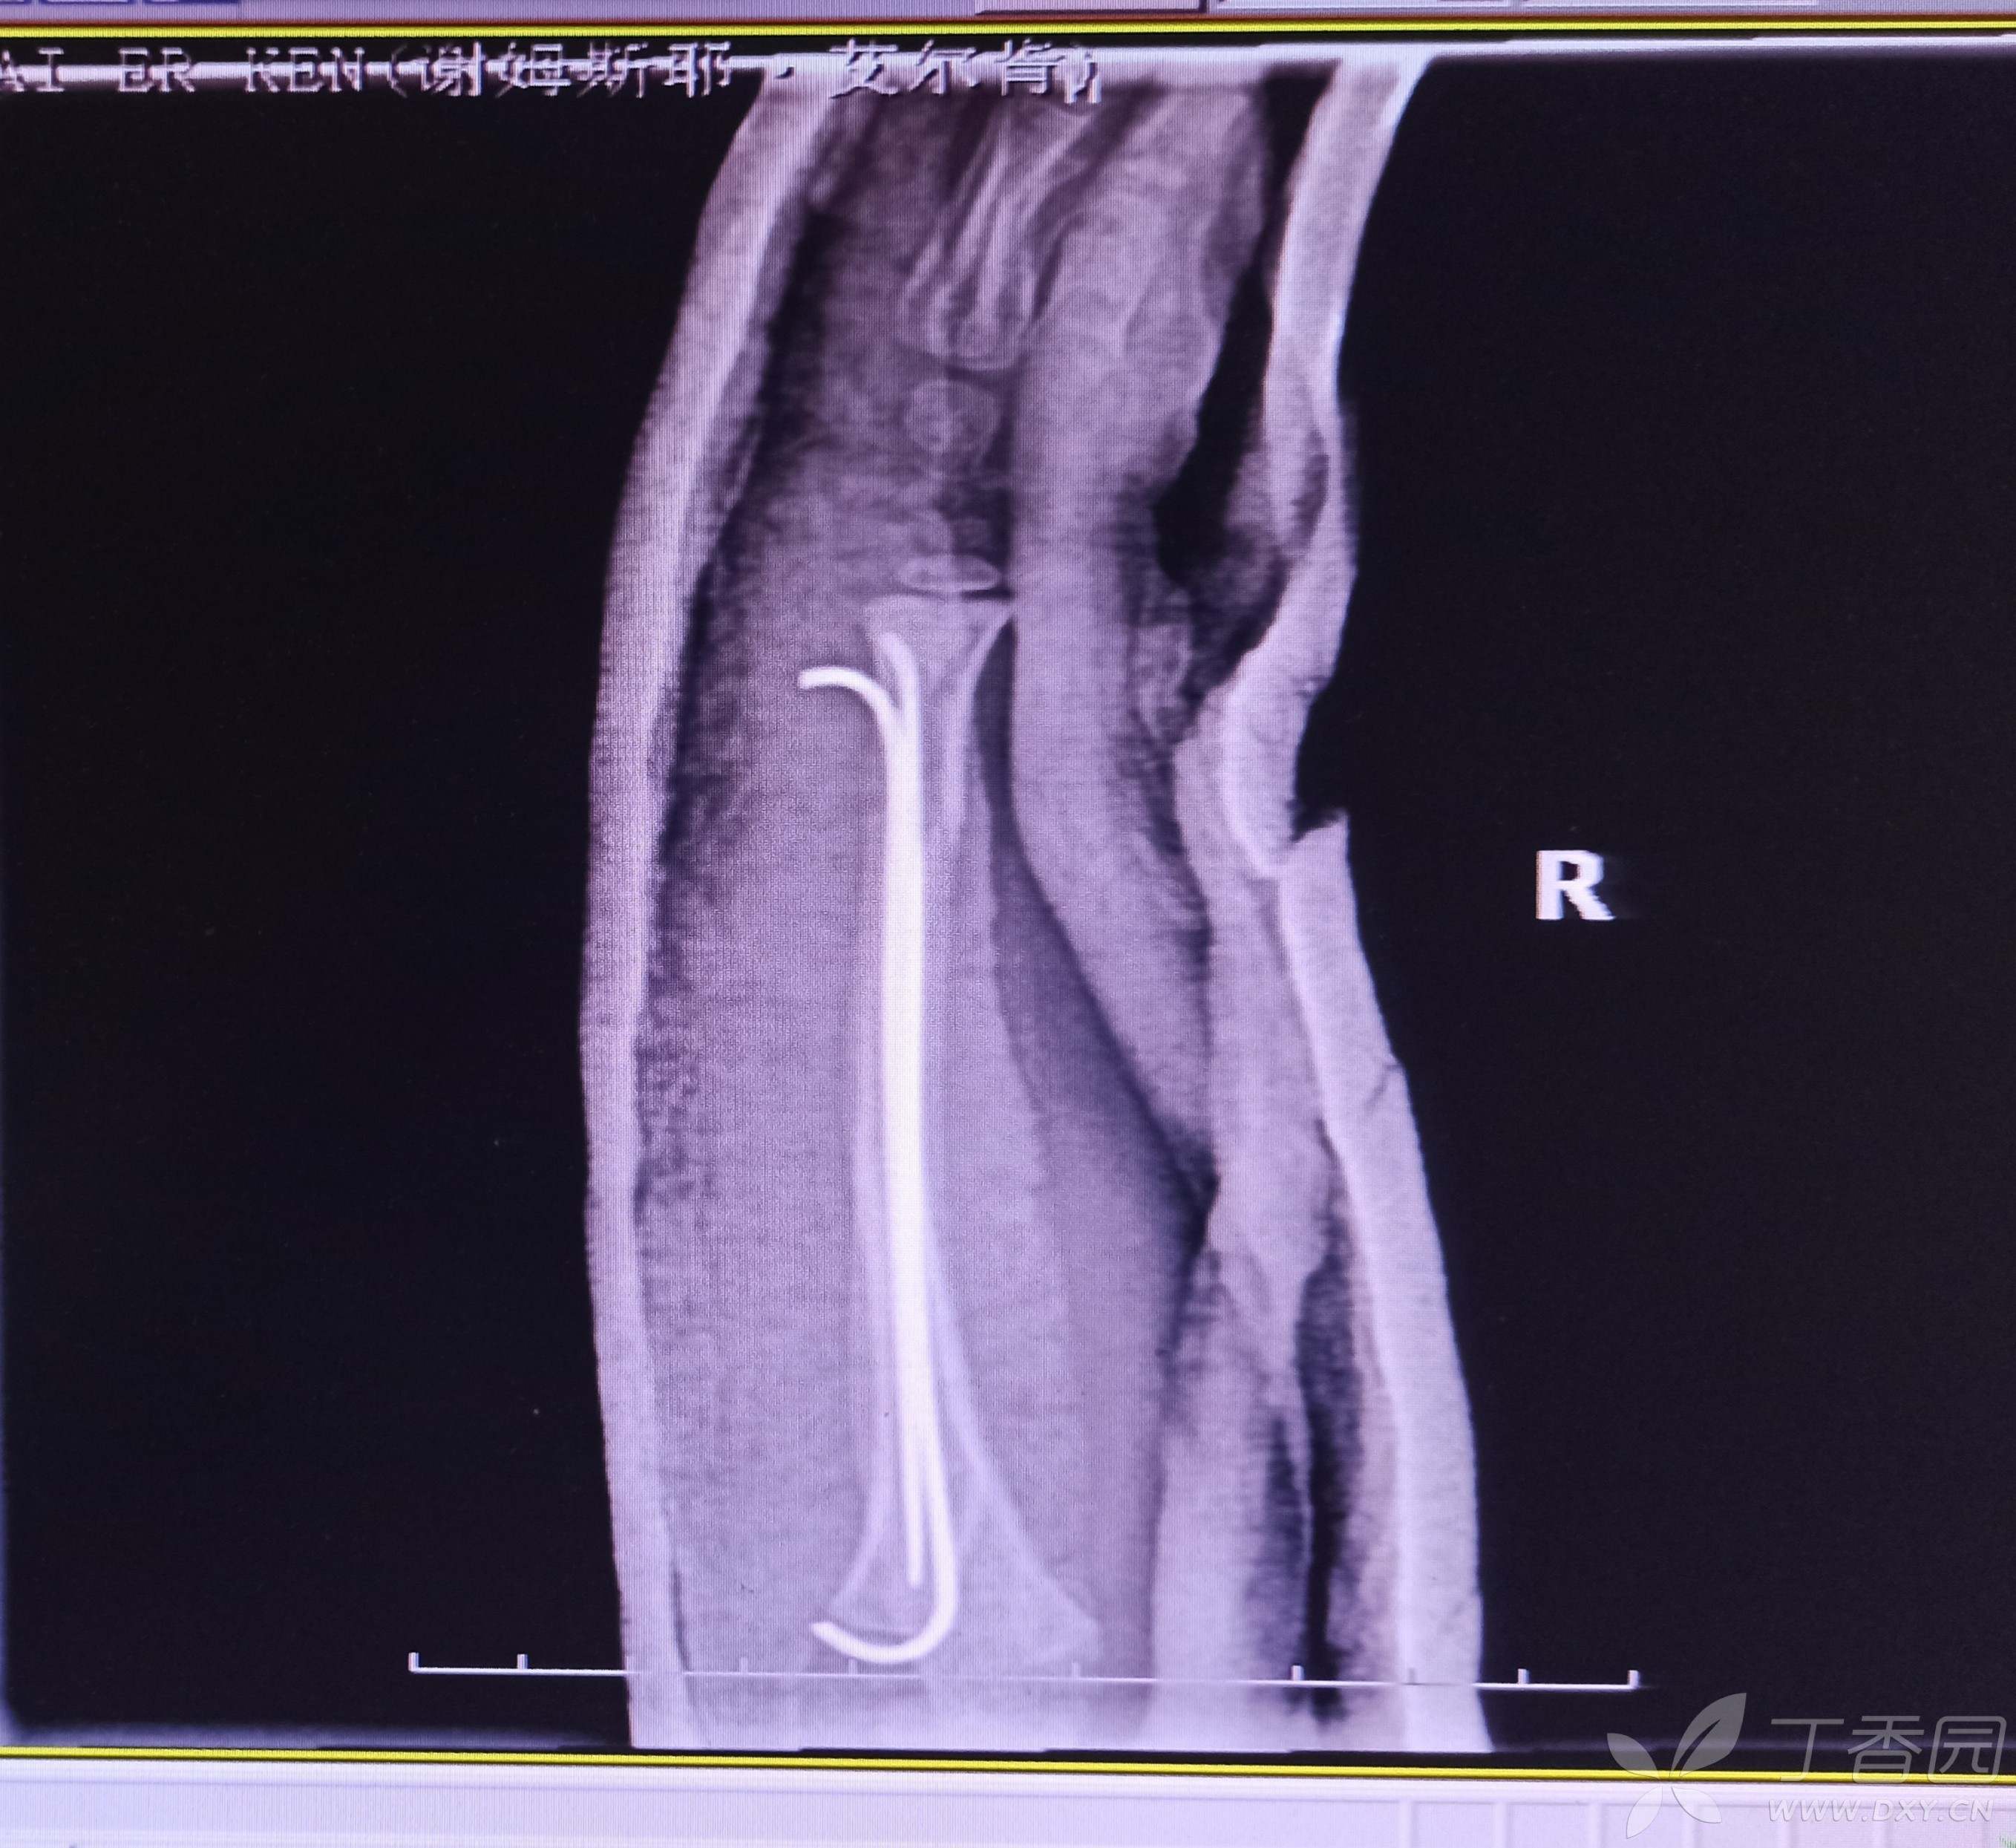

手法牵引复位拍片显示尺骨远端对位对线欠佳,下尺桡关节有分离,给予行弹性髓内钉内固定。遇到这样的各位老师保守还是手术?